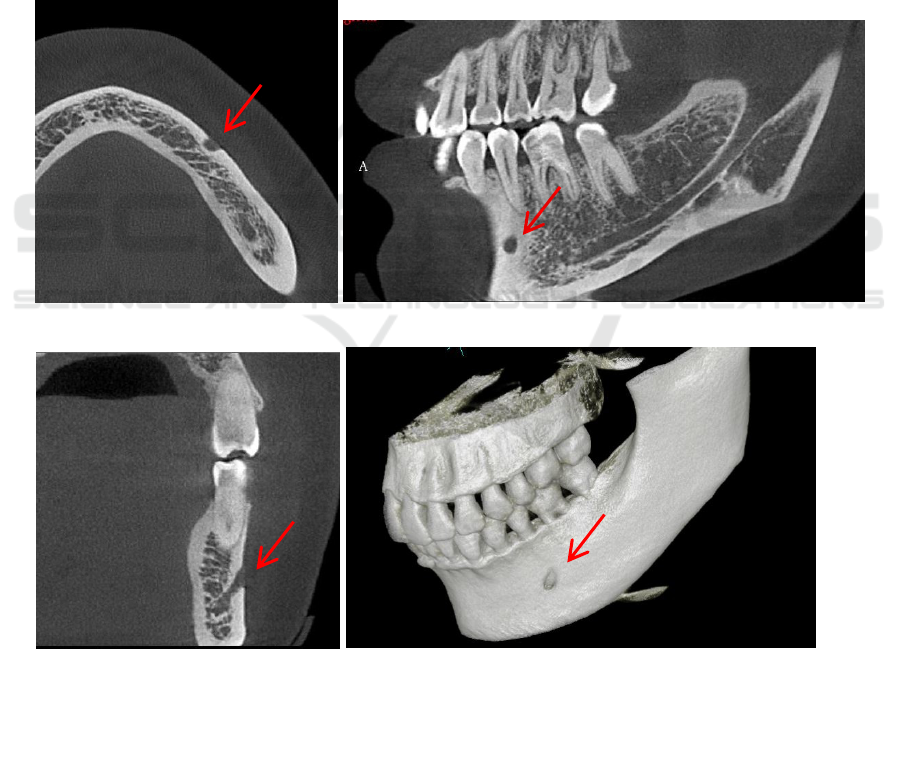

In terms of the integrity of the mandibular canal

observation, we marked the mental foramen on the

side of the jawbone clip as the anterior opening of the

mandibular canal, as shown in Figure 1; the

mandibular foramen on the lingual side of the jaw was

marked as the posterior opening of the mandibular

canal, as shown in picture 2. If the entire structure

between the anterior opening and the posterior

opening of the mandibular neural canal can be clearly

observed in the CBCT image, it is considered that the

entire neural canal can be observed completely;

otherwise, it is considered that the entire neural canal

cannot be completely observed.

Axial

Sagittal

Coronal 3D view

Figure 1: Anterior opening of the mandibular canal (mental foramen).